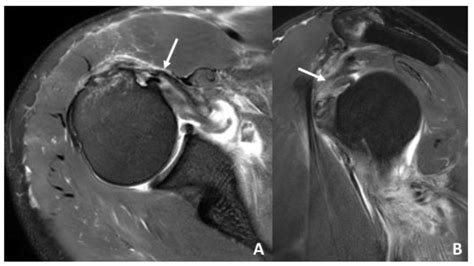

Diagnosing a Dislocated Shoulder Blade

Diagnosing a dislocated shoulder blade involves a combination of physical examination and imaging tests. The healthcare provider will:

• Order imaging tests such as X-rays, CT scans, or MRIs to confirm the diagnosis and assess the extent of the injury.